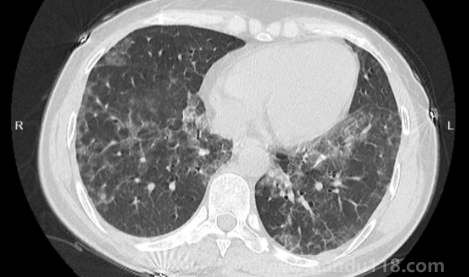

新冠白肺可逆嗎(新冠肺部白化能恢復(fù)嗎) 新冠白肺可逆嗎(新冠肺部白化能恢復(fù)嗎)新冠白肺是比價(jià)常見(jiàn)的一個(gè)癥狀,現(xiàn)在無(wú)論老人還是年輕人如果新冠感染一直咳又不康復(fù)的話(huà),可能會(huì)出現(xiàn)白肺或者肺炎的情況。那么,新冠白肺可逆嗎?84歲老人肺全白有救嗎?一... 小編 2023-01-09 889 #新冠 #白肺

如何自查是否出現(xiàn)白肺(肺白了還能恢復(fù)嗎) 如何自查是否出現(xiàn)白肺(肺白了還能恢復(fù)嗎)白肺是目前很常見(jiàn)的情況,受新冠影響很多老年人都出現(xiàn)了白肺的情況,當(dāng)然也有年輕人會(huì)患上白肺。那么,如何自查是否出現(xiàn)白肺?平時(shí)怎樣保護(hù)自己的肺?一起來(lái)看看天都生活網(wǎng)... 小編 2023-01-06 874 #白肺